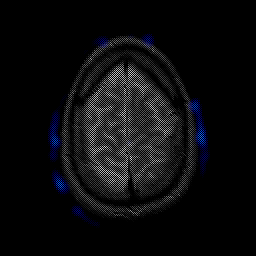

glioma overlay -- Slice #24

[Home][Help][Clinical] Slice 24